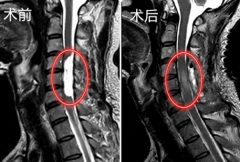

脊柱 医学 手术 2025/08/26

史先生 神经和脊髓 手术 2024/10/22